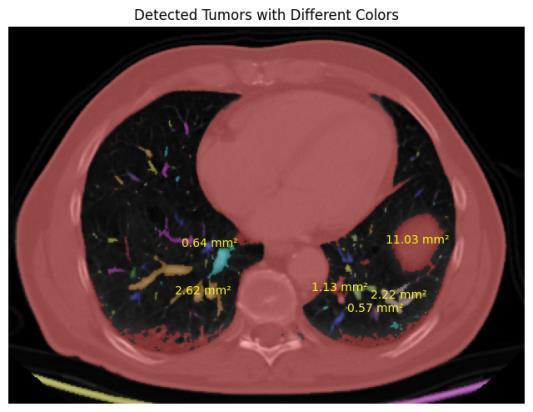

This research introduces an organized and modular method for identifying and measuring tumor nodules in computed tomography (CT) scans by utilizing a blend of image processing techniques and morphological analysis. The proposed methodology aims to pinpoint possible tumorareas,extractpertinentmorphologicalfeatures,and deliver a thorough quantification expressed in medically meaningfulterms.

To start, CT scans are transformed to grayscale to ensure uniform processing. Segmentation of the images is done with Otsu’s thresholding method, which determines the best global threshold level by considering the variance between the foreground and background level of light. This processes aids in separating bright tumor-like regions from the surrounding tissues enabling the formationofabinaryimageoftheareasofprimaryfocus.

Following the segmentation process, individual prospectivetumorsaredistinguishedbythesegmentation oftheconnectedblobregions.Morphologicalattributesof each component are evaluated, including area along with eccentricityandothershapefactors,todistinguishtumorlike structures from non-relevant noisy regions. A filter is applied to retain only those regions whose shapes and complexities coincide with those expected of a tumor, largelyreducingerroneouspositives.

Foreachoftheconfirmedregions,somegeometricvalues representing length, width, radius, diameter and area are captured. These values are then transformed from pixel measurements into standard medical measurement of micrometers, millimeters and centimeters with defined spatial resolution values. This information provides a quantitative assessment of tumor nodules thereby improvingtheirclinicalinterpretation.

The entire catalog of morphological characteristics is structured to give relevant information regarding the size andsculptingofatumor.This,apartfromaidingdetection, will in the future assist in diagnosis, treatment planning, and disease progression monitoring. Moreover, the features which are obtained can be used along with extraction processes to aid in classification and advanced analysispredictiveanalyticsinimaging.